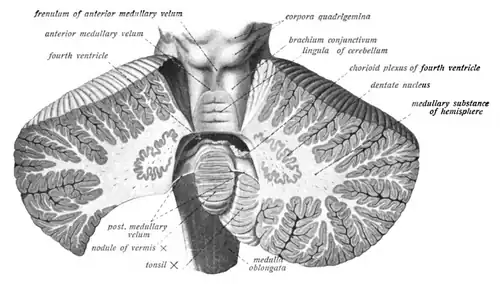

Coronal section of the cerebellum.

Coronal section of the cerebellum. -